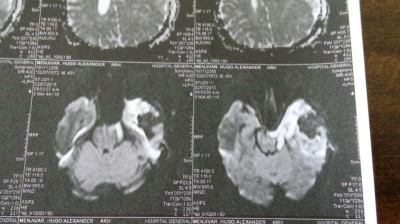

Imagen Post Operatorias 3 días después

Imagen Post Operatorias 3 días despues